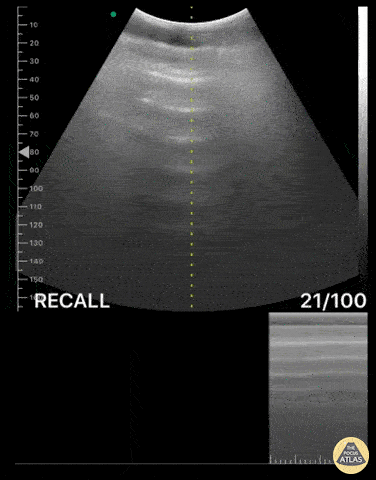

Bowel-GI - Pneumoperitoneum with Enhanced Peritoneal Stripe Sign

Pictured is a transversal epigastric abdominal view, first in M mode and subsequently B mode. Both modes reveal Enhanced Peritoneal Stripe Sign (EPSS), a finding that is highly sensitive and specific for pneumoperitoneum. An A-line pattern is also appreciated in this clip, due to reverberation artifact caused by the free air. This pattern mimics the A-line pattern seen in normal lung tissue. We were able to make this diagnosis with a portable POCUS device in the Emergency Department! Renato Tambelli, Emergency Physician @R_Tambelli